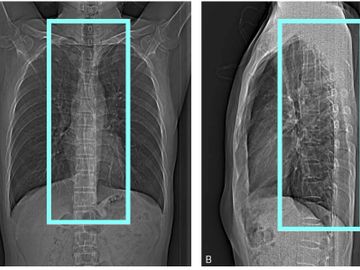

Helical Supine

2.5x2.0 GE bone/2.0x2.0 Siemens bone 2000W 500L

2.5x2.0 Ge standard / 2.0x2.0 Siemens standard 400W 40L

0.625x0.625 GE bone and standard / 0.75x0.7 Siemens bone and standard

Reformats:

coronal 1.25x1mm GE bone and std

coronal 1.5x1.0 Siemens bone and std

sagittal 1.25x1.0 GE bone and std

sagittal 1.5x1.0 Siemens bone and std

angled reformats through each disc space 1mm 15 FOV standard algorithm (if ordered)

VRT rotate and tumble every 10 degrees (If ordered or hardware is present)